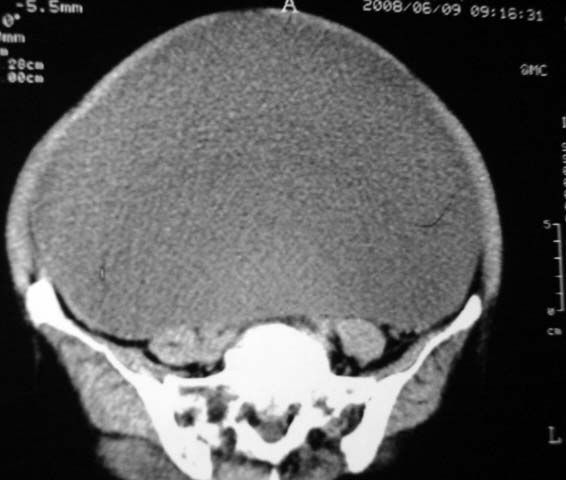

女,75岁,腹部胀大半年余,无其他症状。

考虑来源与卵巢的巨大囊腺瘤或囊肿。

真是腹大如牛,考虑卵巢巨大囊腺瘤或囊肿。

考虑来源卵巢巨大黏液性囊腺瘤。